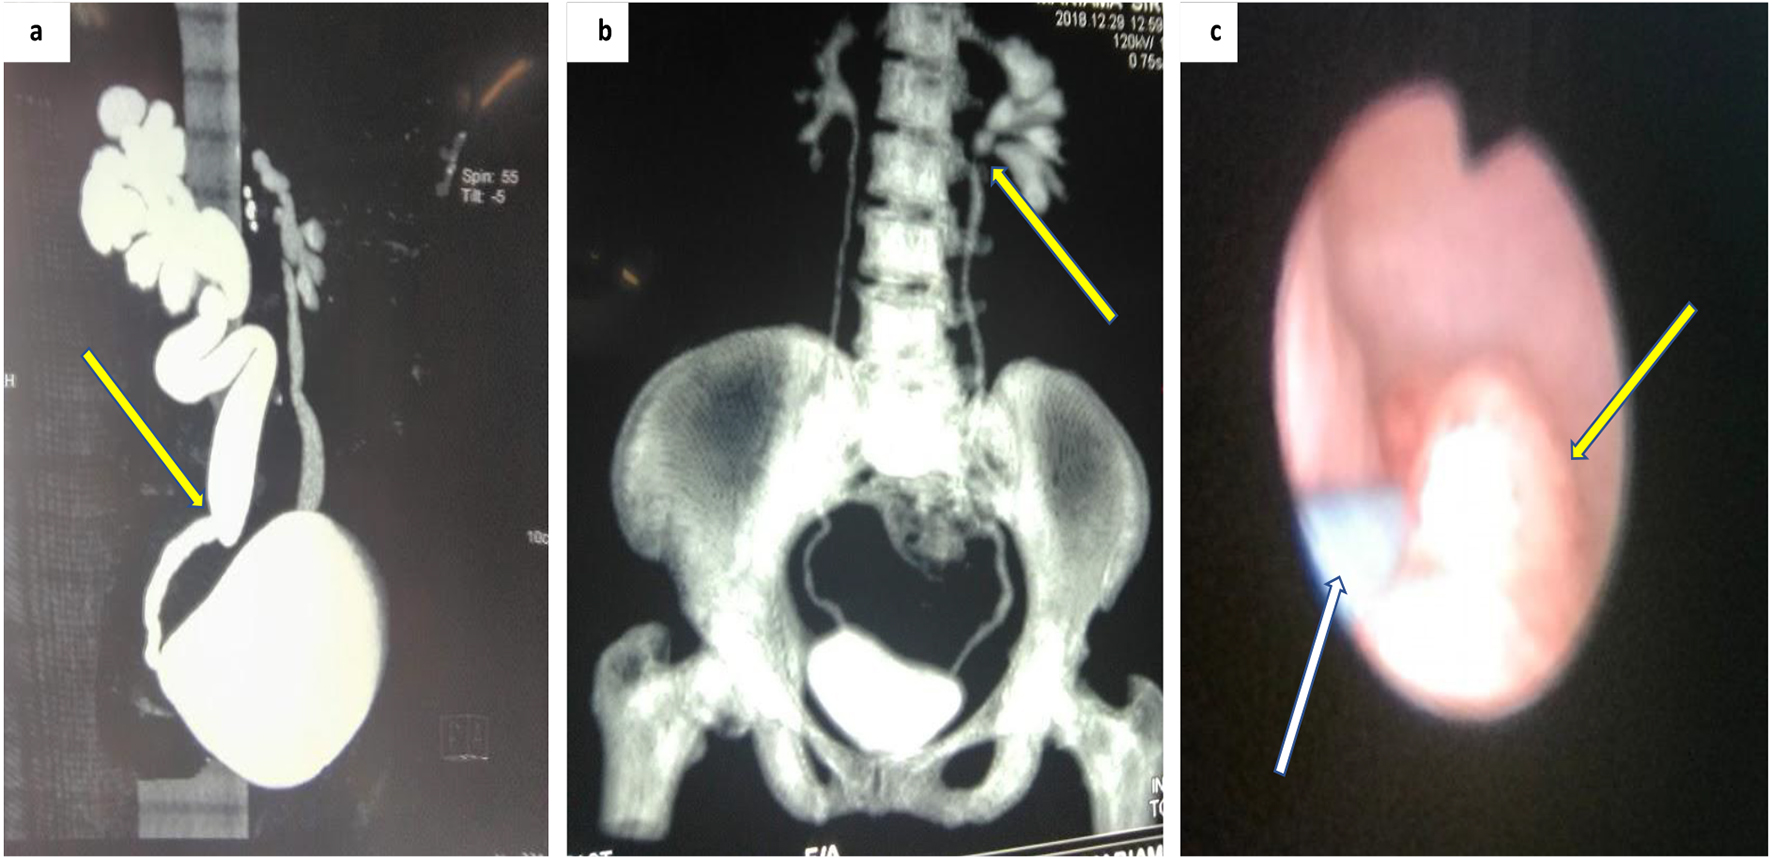

The diagnostic gold standard for UTUC is CT urography with a sensitivity of 67-100% and a specificity of 93-99% [2, 14]. The disadvantage of CT scan is that it may not detect flat epithelial lesion. Findings of hydronephrosis are worrisome and denote advanced disease (Fig. 1a, b).

![]() Click for large image | Figure 1. Imaging of upper urinary tract tumor. (a) CT urography showing suspicion zone of stenosis causing right unilateral hydroureteronephrosis. (b) Coronal view CT urography with filling defect in the proximal left ureters. (c) Ureteroscopy showing a non-obstructing tumor along mid ureters (white arrow showing the guidewire). CT: computed tomography. |

Suspicious lesions on imaging can be biopsied using flexible ureteroscopy (URS) [2]. Patients with solitary kidney or those opting for nephron-sparing surgery are best investigated with flexible URS (Fig. 1c).